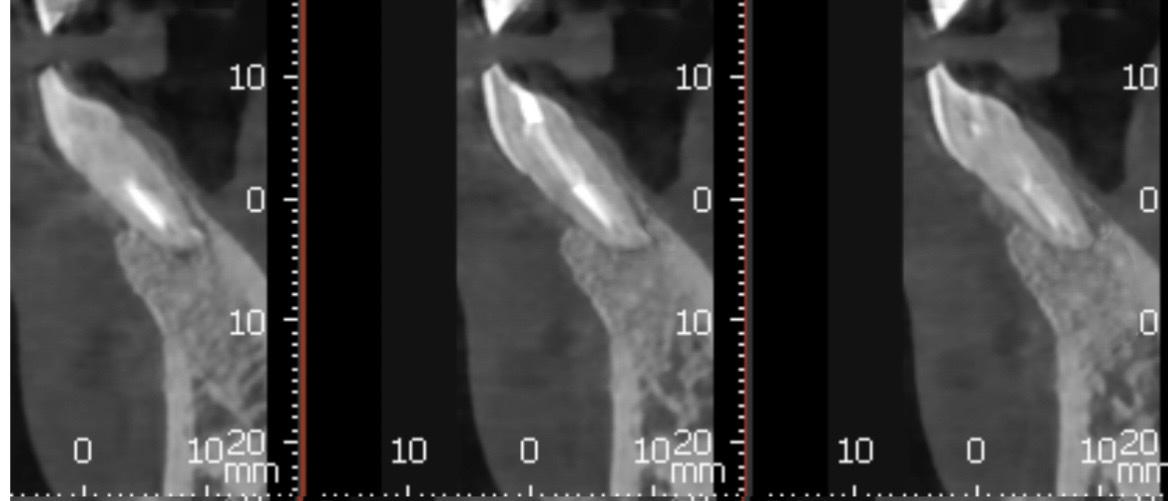

Paciente que tiene absceso a nivel del 41. Se suplementa con OSTEOIMPLANT desde 15 días antes de la cirugía hasta los 3 meses después. La suplementación con Osteoimplant ha ayudado en este caso. En pacientes fumadores la ROG no es tan predecible y en este caso no se ha perdido injerto óseo a pesar de ser una paciente fumadora de 1 caja de tabaco

Se le realiza un TAC donde se observa una imagen radio lúcida de 11,3 mm de ancho y 8,5 mm de largo Esta imagen es compatible con un quiste odontogenico del 41 posiblemente causado por un fracaso endodontico. La imagen radiográfica afecta también al 42 pero dicho diente está vital. Se realiza un colgajo para hacer la quistectomía y apiceptomía del 41. Se regenera con hueso autólogo: xenoinjerto en una proporción 70:30 y membrana de colágeno STD de media reabsorción.